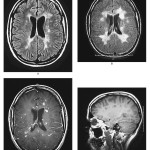

מחלת האלצהיימר תוקפת אחד מכל חמישה אנשים. הדרך לאבחן את המחלה ולהבדיל אותה ממחלות דמנציה אחרות איננה פשוטה- כיום הנוירולוגים מאבחנים אותה על-ידי מבחני הגיון וזיכרון ודיווחים על הסתגרות חברתית. בעשור האחרון פותחו סריקות מוח של PET (פליטת פוזיטרונים), כשהפיתוח האחרון משתמש בחומר צבע רדיואקטיבי בשם “אמיוויד”.  חומר זה מתרכז ברבדי  העמילואיד,  החומר החלבוני המצטבר… המשך הקריאה